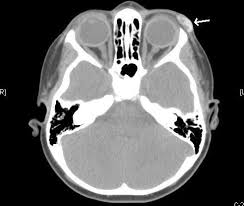

Hair Artifact Radiology Reference Article Radiopaedia Org

Hair Extensions On Ct Scan Of Brain Slow Youtube

What The Heck Head Ct The Answer The Trauma Pro